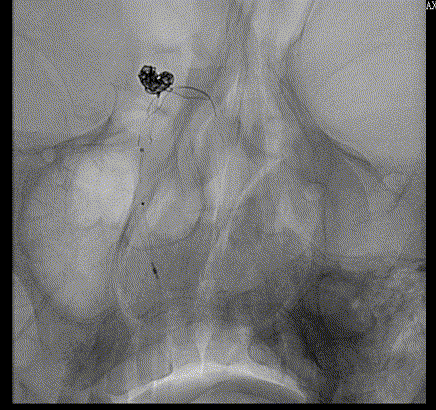

畅医达(TaminoVIA)颅内动脉瘤辅助栓塞支架完全释放,打开效果好,显影清晰,瘤体部分显影

术后造影显示动脉瘤囊闭塞,畅医达(TaminoVIA)颅内动脉瘤辅助栓塞支架形态良好,载瘤动脉通畅